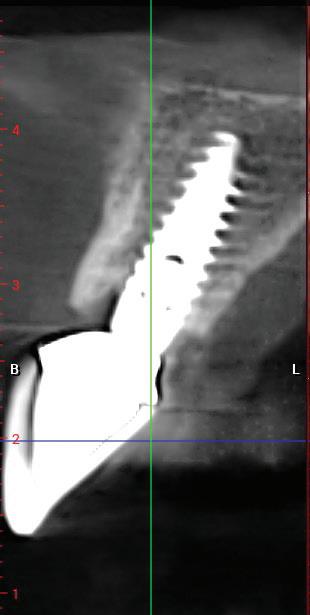

De asemenea, trebuie evaluate anual modificările radiografice. În ședința de inserție a restaurării, se înregistrează o radiografie bitewing standardizată pentru a permite evaluarea anuală a modificărilor osoase din jurul implantului. Remodelarea osului alveolar în primul an este bine documentată și depinde de tipul de implant utilizat; cu toate acestea, nu ar trebui să apară apical de primul filet al implantului. Prin urmare, este importantă abilitatea de a vizualiza filetele implantului pe radiografii. Modificările pierderii osoase de 2 mm sau mai mult după primul an reprezintă un semn de periimplantită. De îndată ce pierderea osoasă este recunoscută, pacientului trebuie să i se recomande terapia imediată pentru a opri procesul de boală.

Utilizarea platform-switch și-a dovedit eficiența în sistemele moderne de implanturi. Însă acum, zona conică inversată oferă mai mult spațiu și un suport mai bun de aderență pentru țesutul dur și moale decât formele cilindrice ale implanturilor, așa cum cum se poate vedea în imaginea următoare.

Suprafața microstructurată din zona conică inversată sprijină atașarea osului și a țesutului conjunctiv. Atunci când marginea acesteia este poziționată subcrestal, este recomandată utilizarea unui material de augmentare (xenogrefă sau os autolog) care poate preveni dezvoltarea țesutului moale în zona conică inversată și poate oferi suport pentru o mai bună osteointegrare.

ția clinică, de la restaurarea unui singur dinte până la reabilitarea arcadelor, cu ajutorul tratamentului SKY fast & fixed se poate observa formarea de os nou. Înălțimea crestei alveolare se păstrează cu ajutorul osului nou format în zona conică inversată, deoarece există o indicație redusă pentru regularizarea osoasă a sitului implantar. Conceptul de creștere osoasă reprezintă exact etapa următoare de dezvoltare a platform switch: designul implantului și al bontului, conul inversat microstructurat și poziționarea subcrestală a implanturilor copaSKY acționează sinergic nu numai pentru a preveni resorbția osoasă, dar și pentru a sprijini regenerarea osoasă.

Studiile și experiența clinică au demonstrat faptul că prin poziționarea subcrestală a implantului copaSKY se poate obține mai mult spațiu în zona gingivală pentru atașarea țesutului moale și remodelarea țesutului osos.

1. Implanturi din titan (stânga) și zirconiu (dreapta). 2. Recesii la implanturile ceramice (stânga) și din titan (dreapta). 3. Țesut moale cu implant din zirconia, lipsit de inflamație.